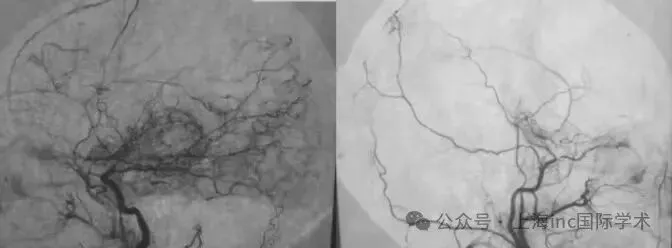

烟雾病是一种罕见的慢性进行性脑血管闭塞性疾病,其特征表现为颈内动脉远端和大脑中动脉主干逐渐闭塞,脑底部形成纤细的“烟雾状”侧支血管进行代偿供血,在血管造影影像上呈现“烟雾”样表现,故得此名。

手术方式采用STA-MCA吻合术。鉴于头痛源于脑缺血,根本解决方案是重建稳定的供血通道。该手术原理是将头皮血供丰富的颞浅动脉直接吻合到大脑表面缺血的大脑中动脉分支,相当于在堵塞的主干道旁建立新的血流通道,使血液绕过堵塞点直接灌溉缺血的大脑皮层。